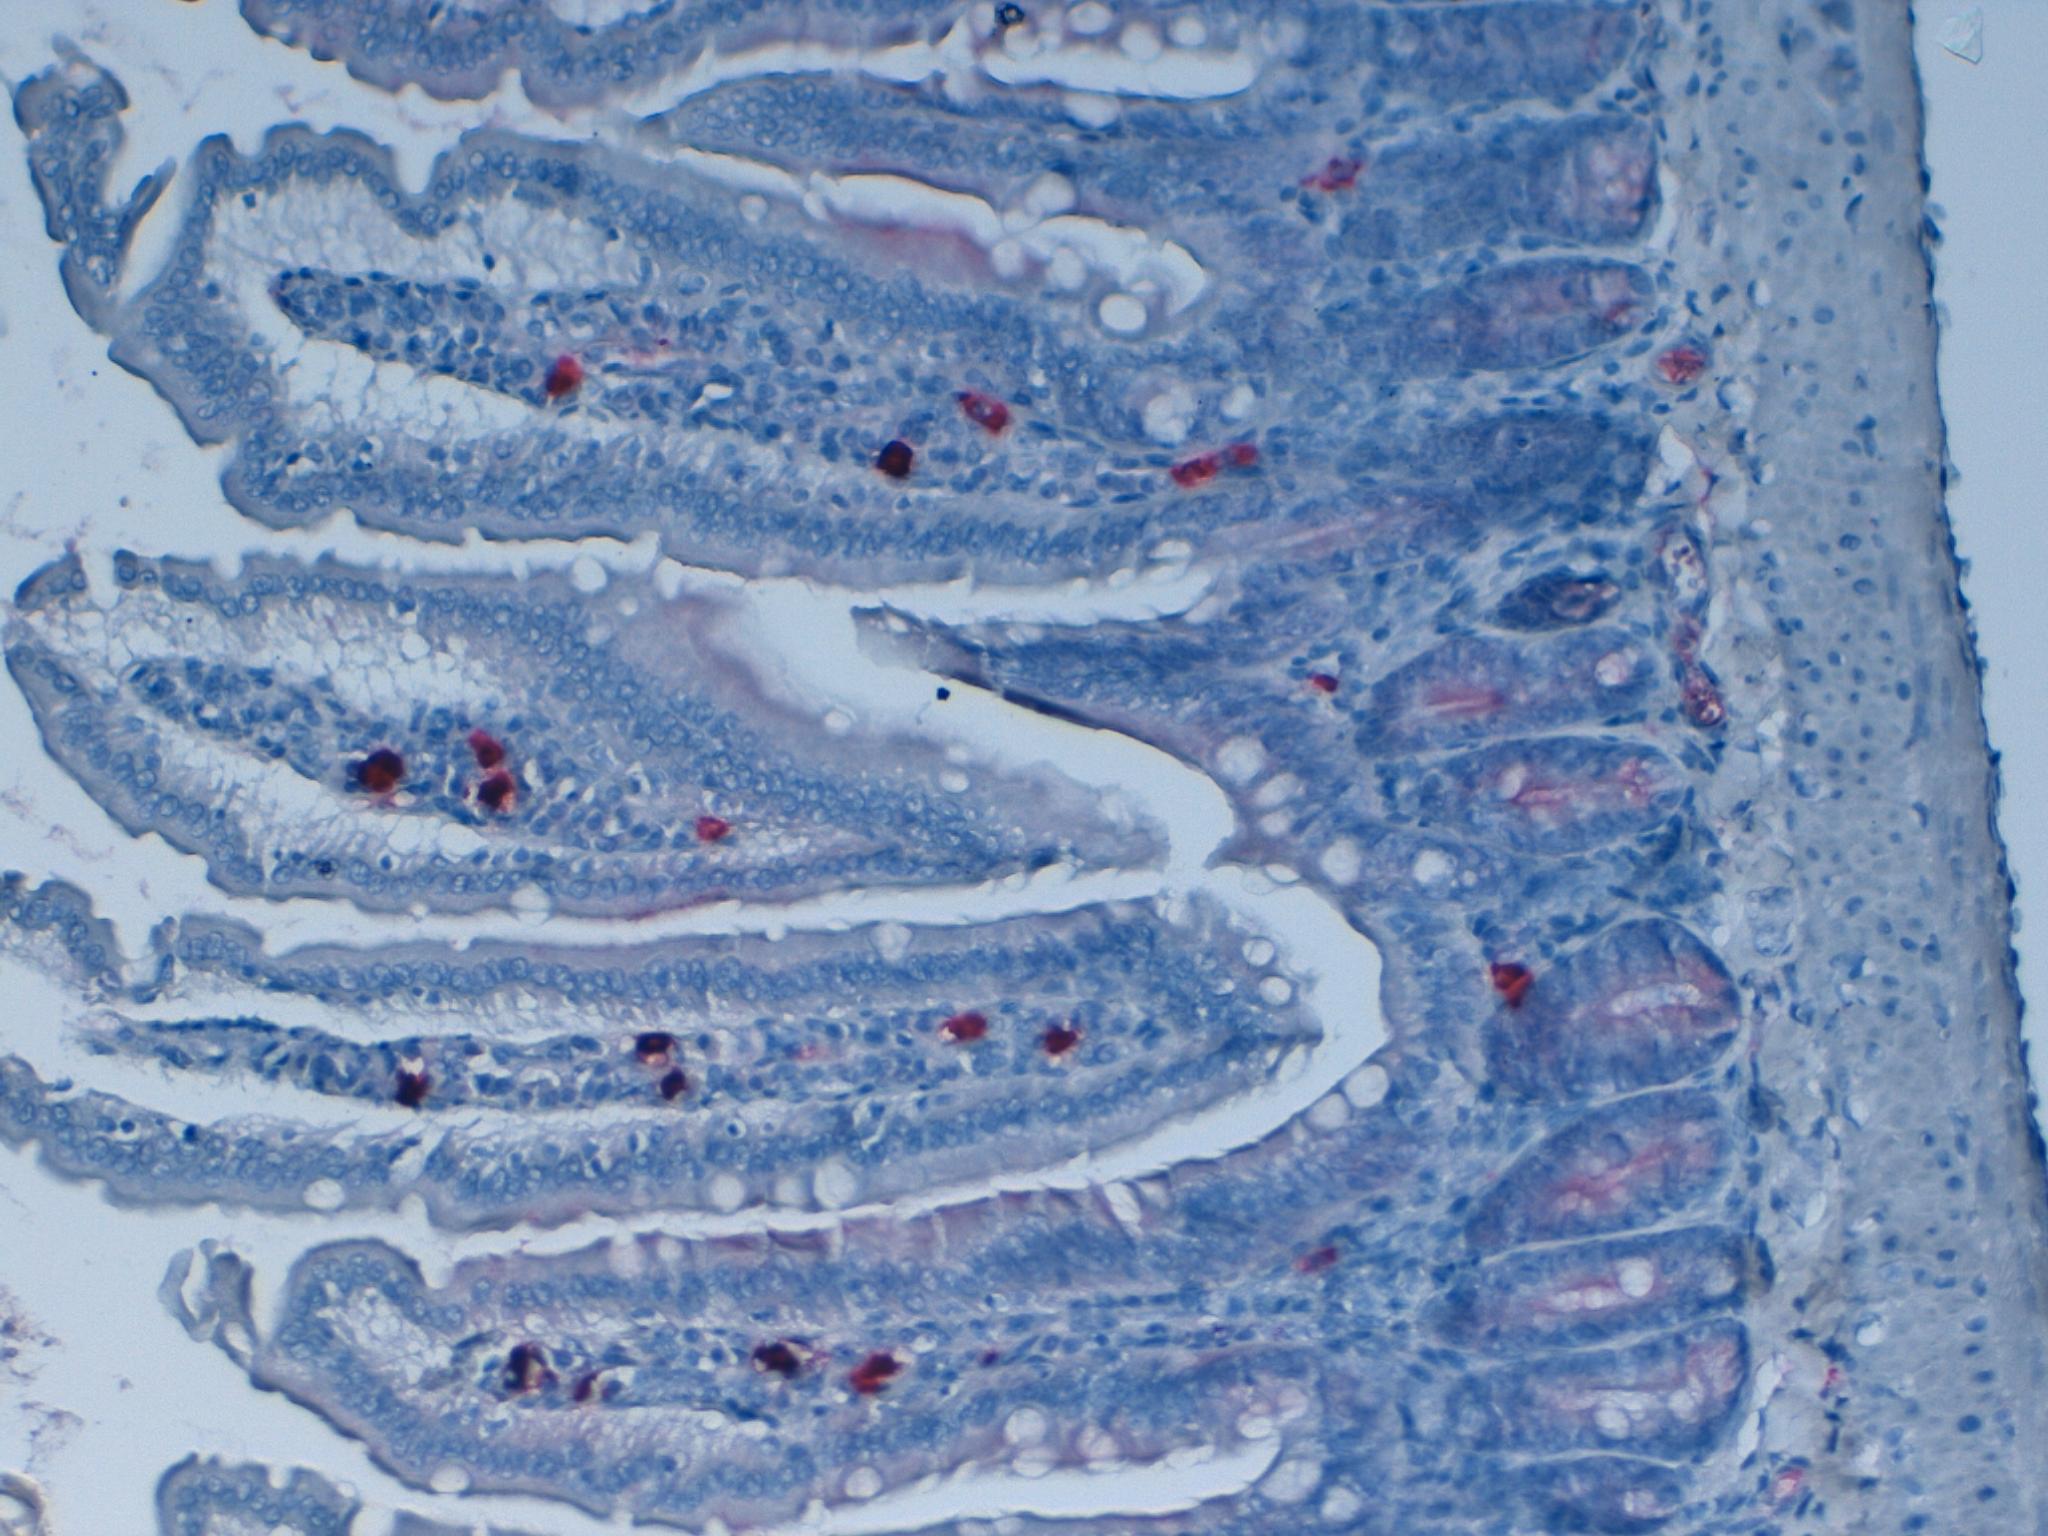

KI67 Mouse Intestine 20X

KI67 Mouse Intestine 10X

Ki67 and Caspase 3 - Double Staining 20x

Ki67 and Caspase 3 - Double Staining 10x